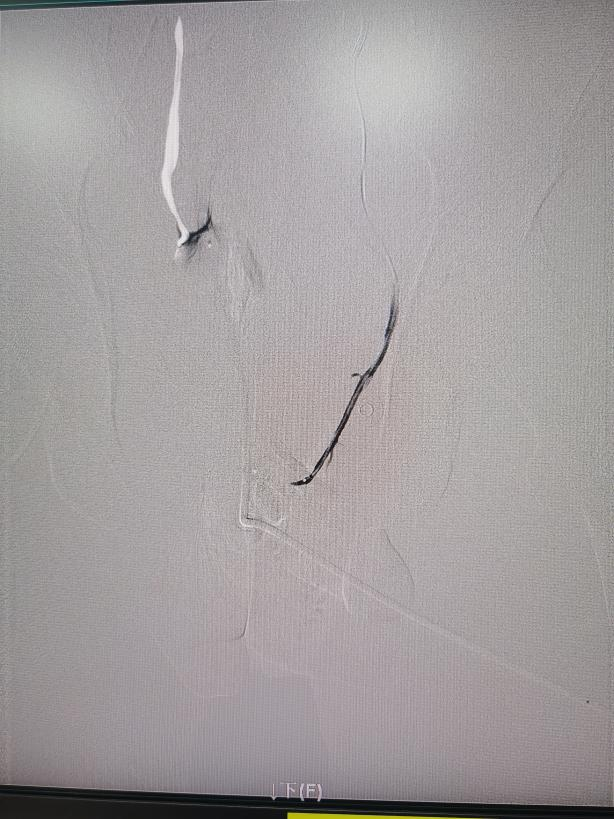

手术中,介入治疗医学中心主任罗阳带领医师林杰、李思刚,借助DSA影像实时引导,精准锁定左侧髂内动脉远端分支的出血点。

面对骨盆骨折后复杂的血管情况,专家们精细操作,如 “穿针引线” 般直达出血分支,用明胶海绵颗粒成功堵住 “漏水口”!术后造影显示,靶血管血流截断,外溢征象完全消失。出血完全停止,手术非常成功!